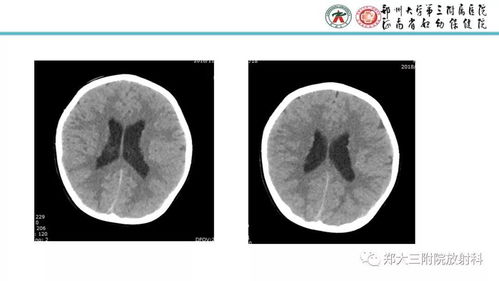

灰质是中枢神经系统内神经元细胞体集中的地方。

由神经元细胞体、树突及与之联系的神经末梢和胶质细胞构成。

富于血管,在新鲜标本上呈暗灰色。

灰质由神经元,神经胶质细胞,毛细血管组成。

灰质的灰色产生与神经元的细胞体和毛细血管。

中枢神经系统的另一个重要组成部分为白质。